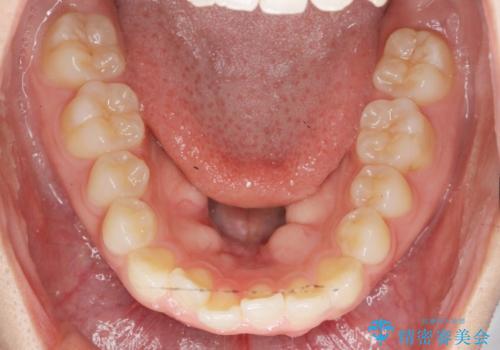

前歯のすれ違い インビザラインで行うマウスピース矯正

- 前歯のガタつき、でこぼこ、前後が逆になっている噛み合わせの改善を求めて来院されました。

治療の装置が目立たず歯ブラシのしやすいマウスピース矯正インビザラインでの治療を計画します。

20時間/日の装用時間をしっかりと守っていただき、きれいな歯並びを手に入れることができました。